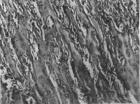

骨质含的胶原为I型胶原。胶原细纤维普遍呈平行排列,但也分支,交互连接成错综的网状结构。胶原细纤维的直径和其他种类有很大不同,但一般说,随年龄增长,直径逐渐增粗,显得更密集。

(5)无机物:骨基质中的无机物通常称为骨盐,在电镜下呈细针状结晶。这些骨盐结晶大都沉积在胶原纤维中。结晶衔接成链,并沿纤维长轴呈平行排列,其排列方向显示出很强的抗压力效能。